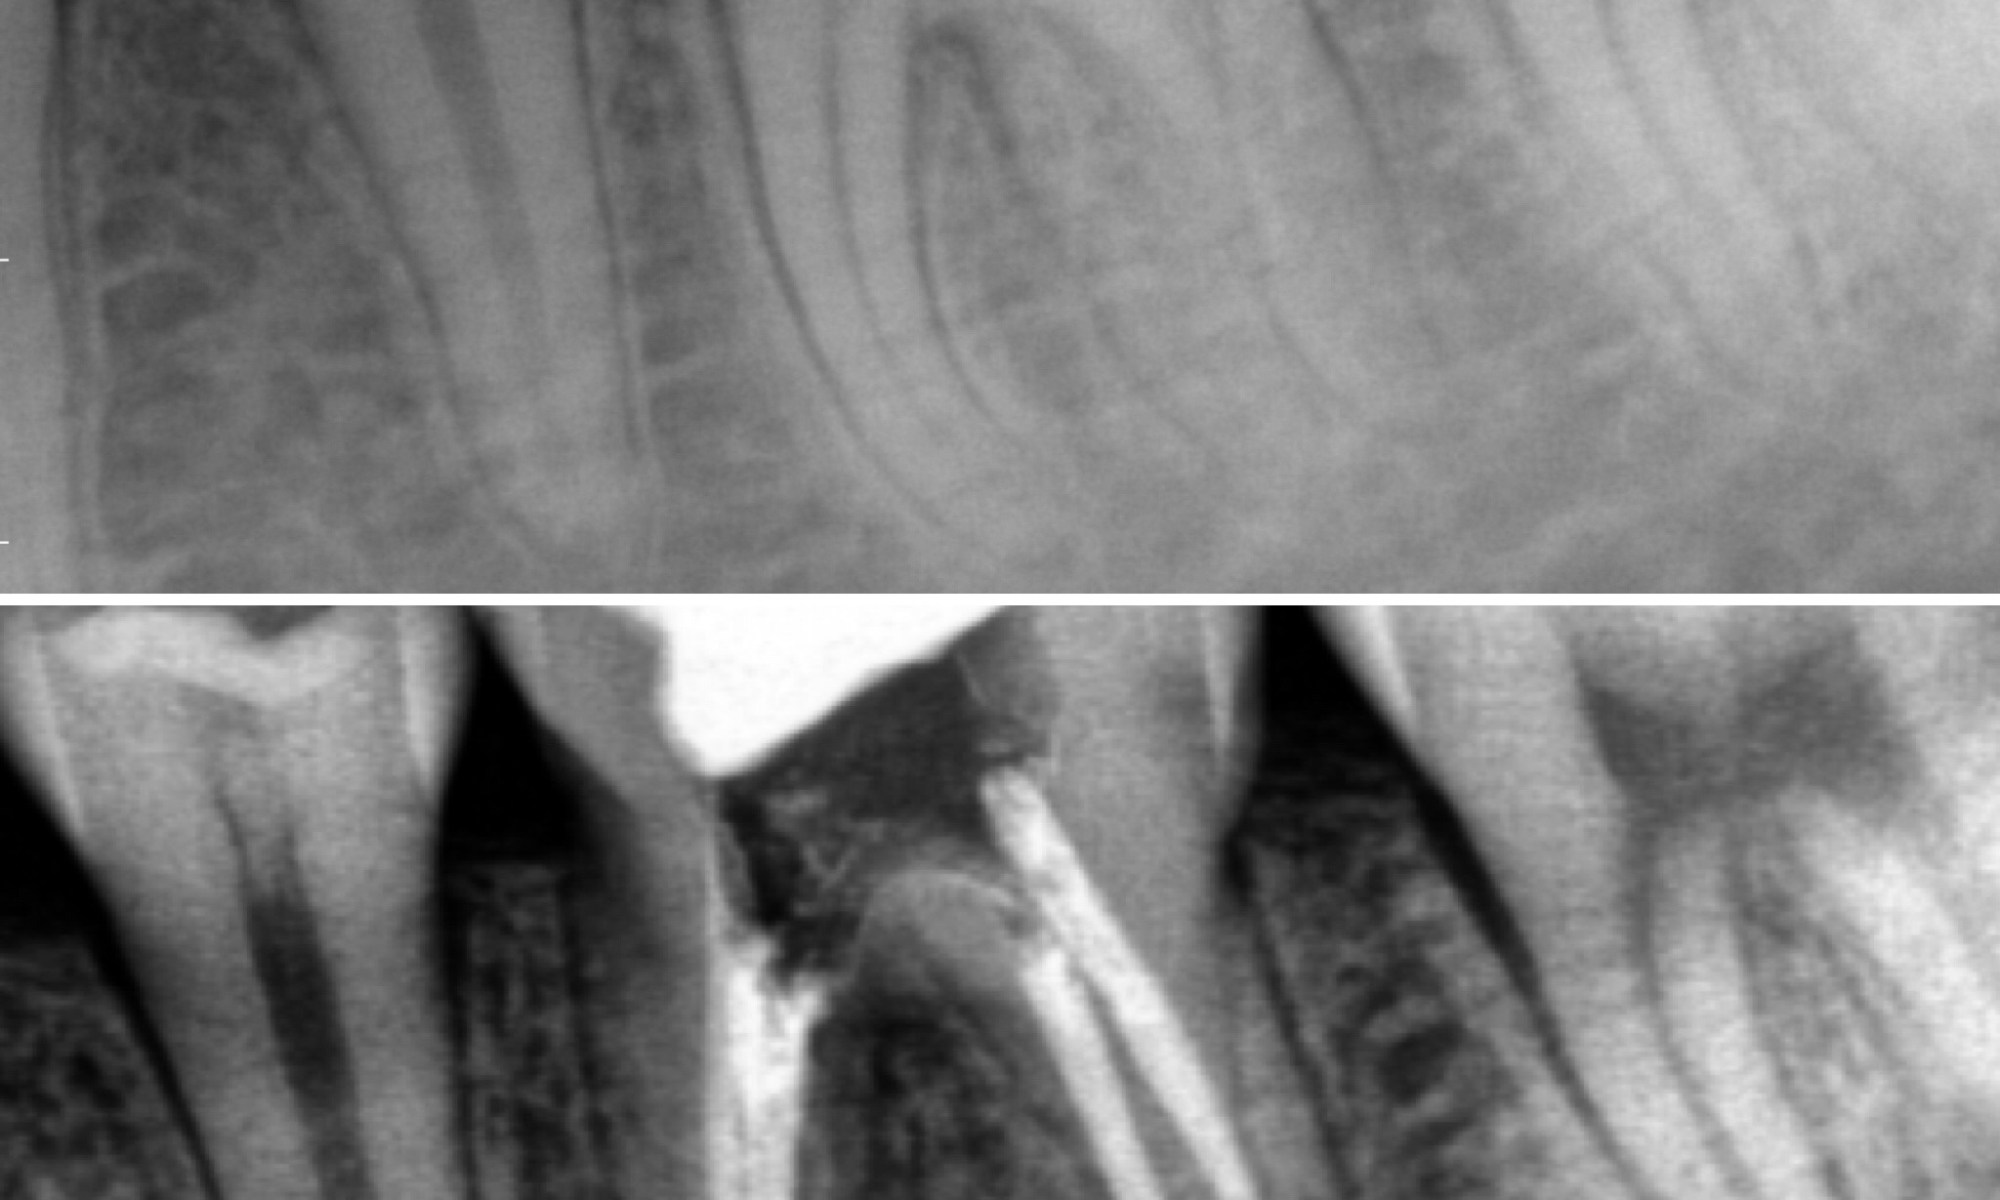

It’s hard to see, but sometimes a tooth can have 5 canals. This tooth was causing a young boy major. Bacteria in the mouth created a hole underneath a filling. A single visit root canal was performed and filled. Pain was relieved.